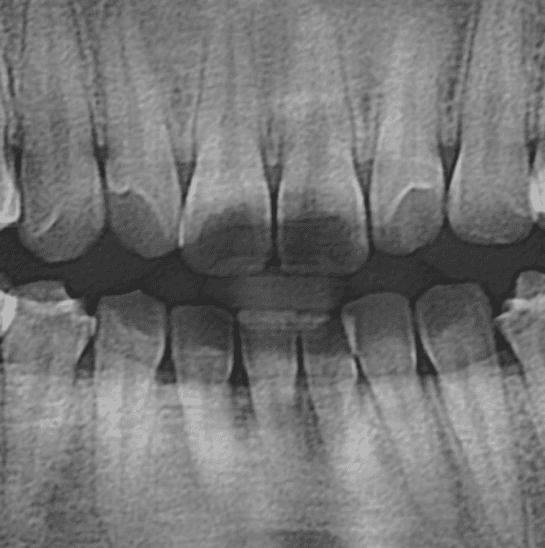

Panorama X-ray

X-ray로 찍은 파노라마 영상을 병원 서버에 자동으로 업로드하여, 치과 우식증(Caries), 치근단치주염(Apical periodontitis) 의심 부위와 치조골 레벨,신경 치료, 임플란트, 보철물 등을 실시간으로 표기할수있는 파노를 소개합니다.